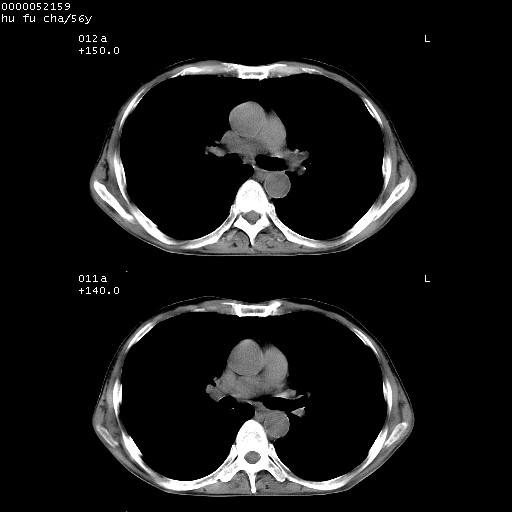

以下是引用zsl6918在2008-8-25 22:47:00的发言:[br]胸骨,胸椎及肋骨均可见多发转移表现,肝内低密度结节不除外转移。原发灶可能在右肺。双侧可见支扩表现。